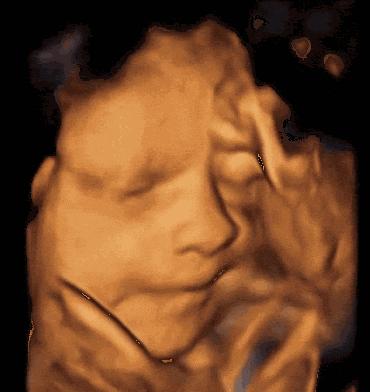

《孕前和孕期保健指南》建议孕妇在第三次孕检:20-24周时,进行系统超声筛查,就是我们俗称的“四维彩超”,大排畸筛查。

四维是高清动态的彩超,可以拍下胎儿的照片。但三维在筛查效果上,与四维并没有多大区别。

单胎建议孕24周做四维,双胎或多胎建议孕22周做四维。

四维不适宜过早或过晚做。过早做,胎儿小,看不清楚相关器官和肢体。太晚做,胎儿在体内长大了,不便于胎儿翻身让医生看到其他部位;同时,如果发现畸形,也耽误了治疗或处理的时间。

大排畸可以排除无脑儿、脑积水、肠道闭锁、肾积水、短肢畸形、部分先天性心脏病等。

但不能筛查:骨发育不良(需32周产科胎儿生长测量超声检查)、复杂心脏畸形、60%染色体疾病、智力、听力、视力的功能异常等。